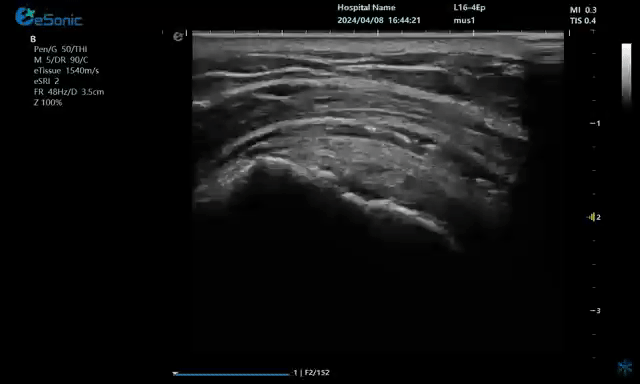

一、超声引导下注射准确性在尸体上研究

在超声引导下注射准确性尸体研究方面,以美国MavoClinic的康复医师SmithJ和FinnoffJT为代表的肌骨超声的开拓者们,做了大量的开创性研究工作,奠定了超声引导下注射准确性的科学基础。